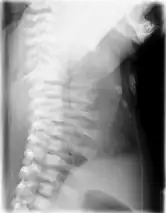

Lateral CXR of the same person above

Jeune syndrome is a rare genetic disorder that affects the way a child's cartilage and bones develop. It begins before the child is born and primarily affects the child's rib cage, pelvis, arms and legs.[5] Usually, problems with the rib cage cause the most serious health problems for children with Jeune syndrome. Their rib cages (thorax) are smaller and narrower than usual, which inhibits the child's lungs from developing fully or expanding when they inhale. The child may breathe rapidly and shallowly. They may have trouble breathing when they have an upper or lower respiratory infection, like pneumonia. Breathing trouble can range from mild to severe. In some children, it is not noticeable, aside from fast breathing; however, in others, breathing problems can be fatal. About 60% to 70% of children with this condition die from respiratory failure as babies or young children. Children with Jeune syndrome who survive often develop problems with their kidneys, and over time they may experience kidney failure.[2] As a result, few children with Jeune syndrome live into their teen years. Children with Jeune syndrome have a form of dwarfism. They are short in stature, and their arms and legs are shorter than most people's.[6]

Jeune syndrome is a rare autosomal recessive ciliopathy.[7] This diagnosis is grouped with other chest problems called thoracic insufficiency syndrome (TIS). Diagnosis of Jeune syndrome can be made as early as before birth if signs and symptoms are apparent on an ultrasound; however, diagnosis after birth usually occurs through X-rays and genetic testing, such as the tests found on the Genetic Testing Registry (GTR).[8]